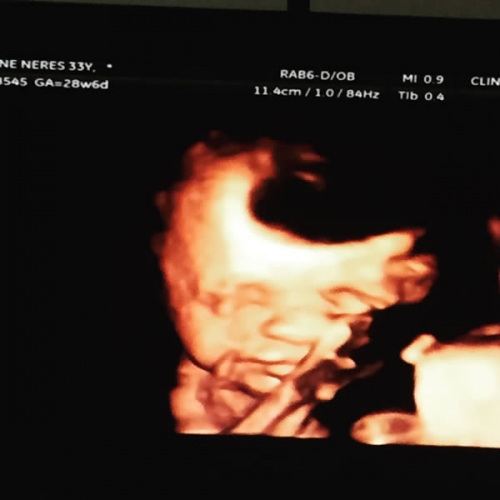

Conheça os exames realizados pela SONNAR!

A Clínica Sonnar preza pela qualidade dos seus exames, modernidade em aparelhos e ótimo atendimento.